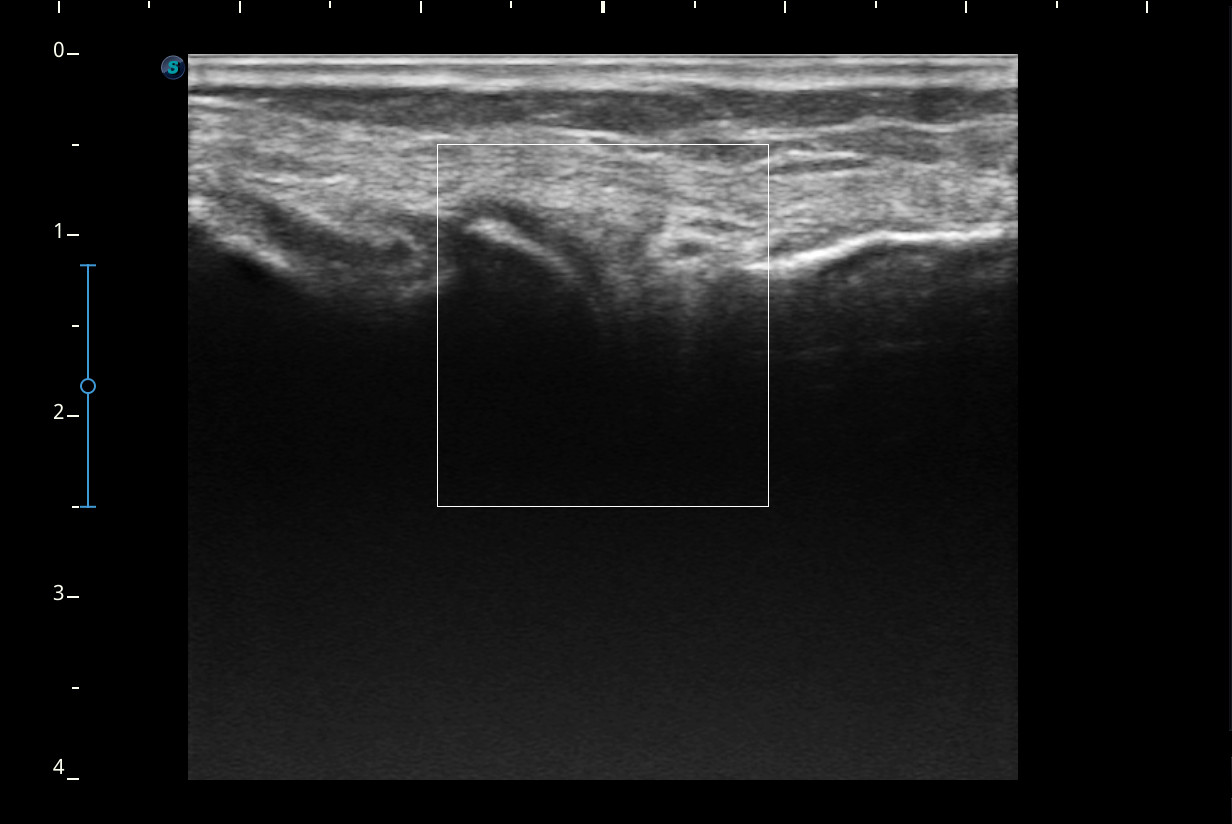

Descripción de los hallazgos ecográficos y las imágenes más relevantes para la resolución del caso

Rodilla sin derrame articular. No se aprecian lesiones en Ligamentos colaterales. Ligamento rotuliano sin hallazgos valorables. Rotura menisco interno y dudosa fisura menisco externo. Tendones rotuliano y cuadricipital normales.